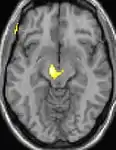

Hypothalamus

La théorie selon laquelle les AVF proviendraient d'une anomalie dans l'hypothalamus[48] est une des plus acceptées ; le Dr Peter James Goadsby[49], spécialiste australien a développé cette théorie. Cette thèse pourrait expliquer pourquoi les maux de tête se produisent avec une chronologie précise et régulière. L'un des rôles de l'hypothalamus est de réguler le rythme circadien. Des anomalies métaboliques ont d'ailleurs été signalées chez des patients.

![]() | ![]() | ![]() |

| La tomographie par émission de positons (TEP) montre les zones du cerveau étant activées durant la douleur | ||

| La morphométrie voxel par voxel (VBM) montre les différences structurelles des zones du cerveau | ||

Les images par tomographie à émission de positron indiquent les régions du cerveau qui sont activées lors de la douleur, par rapport aux périodes sans douleur. Elles montrent les régions du cerveau qui sont toujours actives durant la douleur en jaune/orange (appelé "matrice-douleur"). La zone au centre (dans les trois vues) est spécifiquement activée uniquement pendant la crise. Les photos sur la ligne du bas (effectuées par VBM) montrent les différences structurelles entre les patients souffrant d'AVF et des personnes saines : seulement une partie de l'hypothalamus est différente[50],[51].

Il semble exister des anomalies microstructurales hypothalamiques bilatérales (en l'occurrence l'existence d'une hypertrophie)[52] sans que l'on sache si ces anomalies sont la cause ou la conséquence de la répétition des crises.